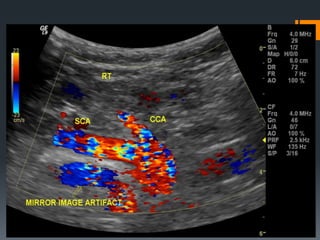

En espejo  Cuandoel haz incide en una estructura curvilínea actúa como interfase especular

Imagen Especular (Ambigüedad direccional) Artefacto del doppler pulsado  Se representa con igual amplitud a ambos lados de la línea base ofreciendo una imagen en espejo  Se produce cuando el ángulo entre el haz de sonido y el vaso es de 90°